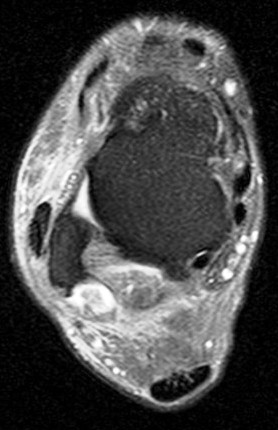

Figure 3 for case peroneal dislocation

Figure 3

Both peroneals are dislocated around fibula. Retinaculum is torn. Initial case was missed. Patient walking around for nearly a year like this.

peroneal dislocation